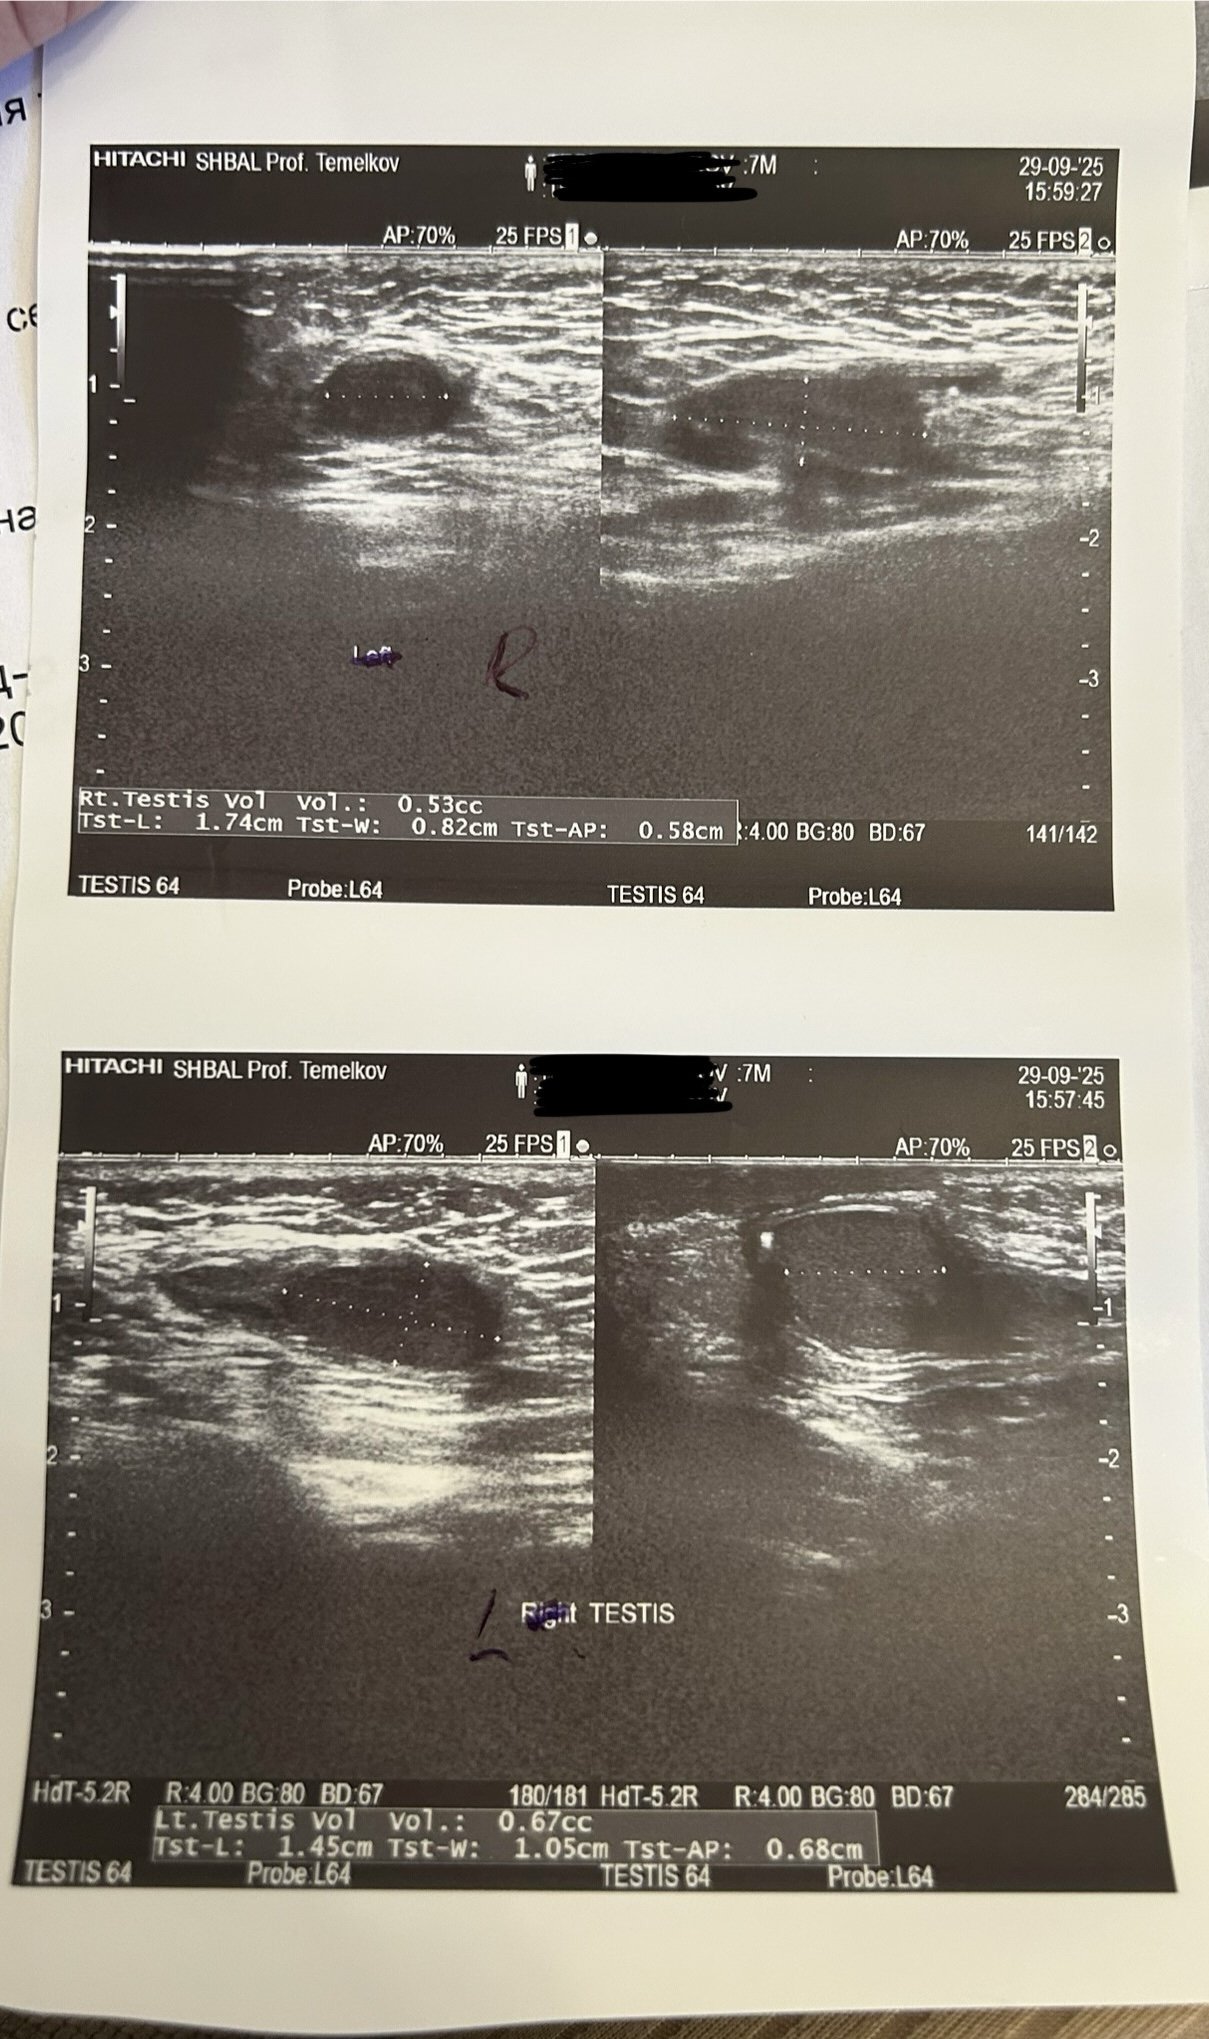

Момченцето ми се роди с едно нормално и едно неслязло тестисче, сега е на 7 месеца. Миналия месец ходихме на консултация при детски хирург във Варна - д-р Румен Христов, който го палпира между ингвиналния канал и скротумната торбичка. Бяхме и на образна диагностика при проф. Балев, който констатира, че тестисът се установява във външния край на ингвиналния канал и мануално се придвижва до входа на скротума, но спонтанно се връща в изходна позиция. Размерите му са - обем 0.53 мл, 1.74 см/0.82 см (на другия тестис са 0.67 мл, 1.45/1.05 см). Казаха ни да изчакаме до навършване на годинка и че все още има шанс да слезе сам, ако ли не - операция. Според Вас наистина ли има шанс да слезе сам? Тези размери сочат нормално развитие, нали? Ако се задържи до годинката опасно ли е? Според Вас добре ли е да дойдем до София за второ мнение и/или операция впоследствие? Ще съм благодарна да чуя Вашето мнение!

Ехографията е точно изследване, но понякога поставянето на маркерите за размери зависи от изследващия. Все пак проф. Балев е светило в своята област. Това, че обемът леко намалява, е част от проблема. Но това не пречи на неговата бъдеща функция.

Общо е прието, че ако тестисът не слезе до 6-ия месец, това е окончателно. Операцията трябва да се извърши не по-късно от 18 месец на детето. Изборът е ваш - д-р Христов е много добър оператор. Ако желаете да дойдете  в Токуда, ще бъде удоволствие за мен до извърша лично операцията.

Имайте пред вид, че по целия свят се отчитат някои усложнения в рамките на 5 – 8% - неуспешно смъкване, повторно връщане нагоре на тестиса, закърняване на неговото развитие. Това зависи от първично нарушената анатомия на кръвоносните съдове или семепровода (т.н. връзки на тестиса или по медицински - кордон). Това обяснявам предварително на родителите и описвам отделните етапи на операцията и следоперативния период.

Впрочем, излишно е да правите повече ехографии.